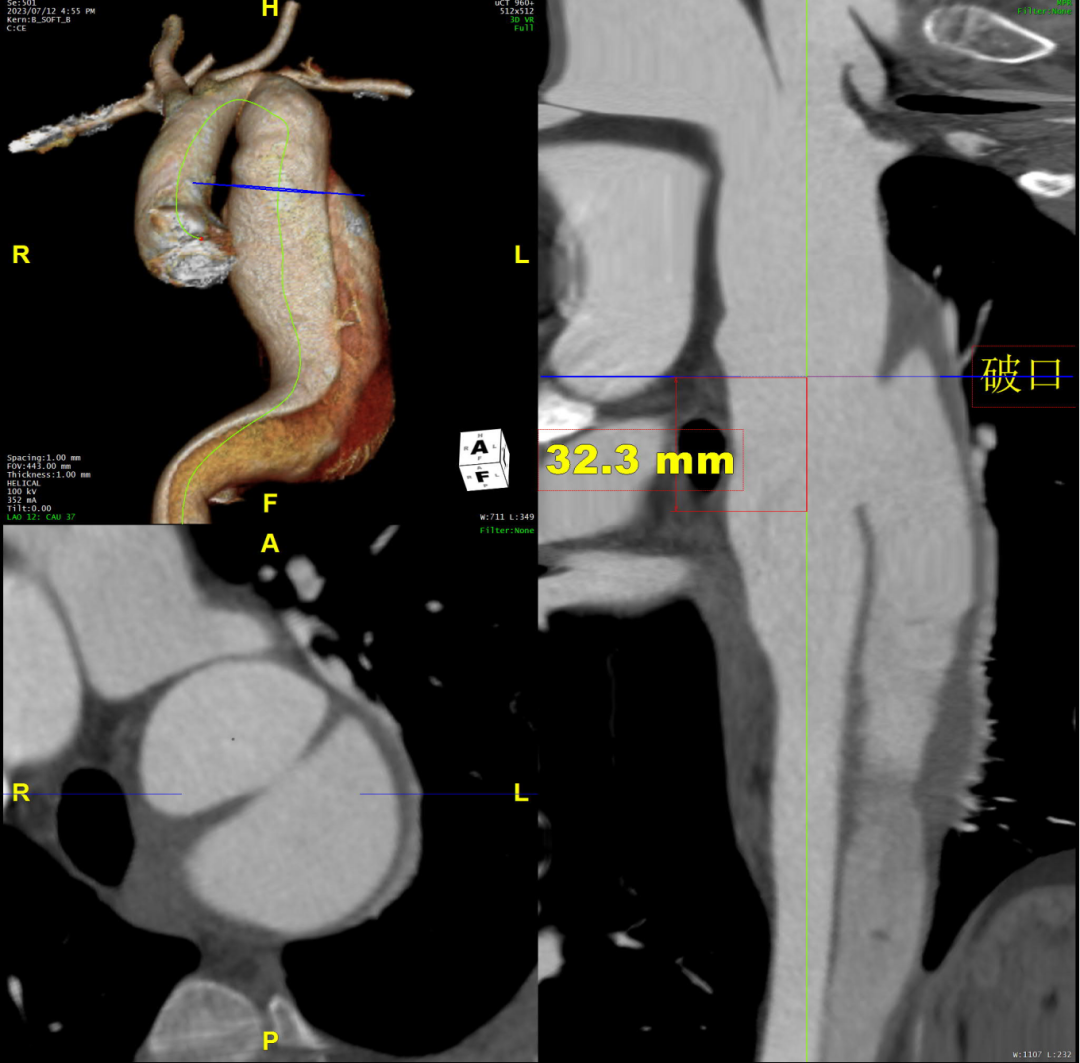

术前CTA评估与测量

术前CTA提示主动脉夹层(Stanford B型,Debake llI型),主动脉弓及降主动脉瘤样扩张,累及左锁骨下动脉起始段,管径最粗约7.4cm,夹层初破口位于降主动脉起始段,向下累及至腹主动脉(约平胸12椎体水平),真腔小,假腔大,腹腔干发自混合腔,肠系膜上动脉、下动脉,双肾动脉均起自真腔,双肾灌注未见差异。

术前三维重建

术前CTA详解:

病例特点

1. 弓型陡峭,成角;

2. 自左颈总后缘小弯侧锚定区不足1cm;

3. 巨大破口,约33mm,病变累及至腹腔干平面。